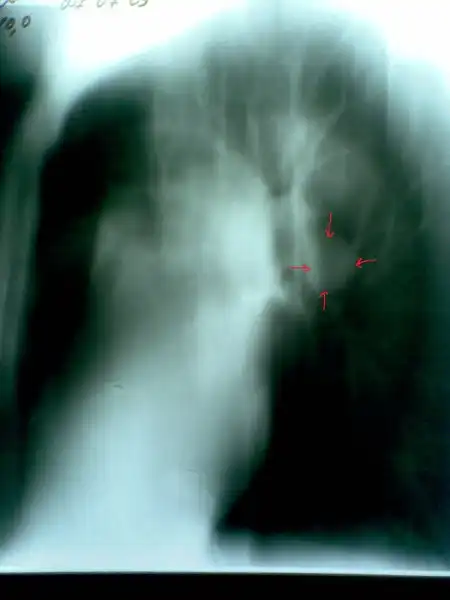

Линейная томограмма: